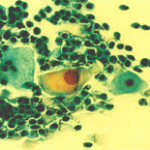

Περιστατικό ασθενούς που παρακολουθείται στο ιατρείο μας από το 1993, τότε ηλικίας 37 ετών, αρχικά λόγω ασυμπατωματικού κυτταρολογικά εμμένοντας έρπητος τραχήλου της μήτρας. Το γεγονός αυτό μας οδήγησε στην διερεύνηση της περιπτώσεως. Η ασθενής επασχε από A.I.D.S.

Είχαμε την ευκαρία να παρακολουθήσουμε ανά 6μηνο γυναικολογικά, κολποσκοιπικά και κυτταρολογικά την γυναίκα από το 1993 μεχρι και το 2008. Από τις εξετασεις αυτές, παρουσιάζουμε χαρακτηριστικές κυτταρολογικές εικόνες . Όι παρακάτω κυτταρολογικές εικονες προέρχονται από την 2η κατά σειρά εξέταση της ασθενούς το 1993. Οι κυτταρολογικές αλλοιώσεις ερπητος συνεχίζουν να υφίστανται.

Ταση γιγαντιοκυττάρωσης όλων των επιθηλιακώ στοιβάδων, κοιλοκυττάρωση, διογκωμένοι υπερχρωματικοί και ανισομεγέθεις πυρήνες , με διάλυση δομής χρωματίνης, συχνά διογκωμενοι πυρήνες με εικόνα φαινομένου ΄΄θολού γυαλιού΄΄